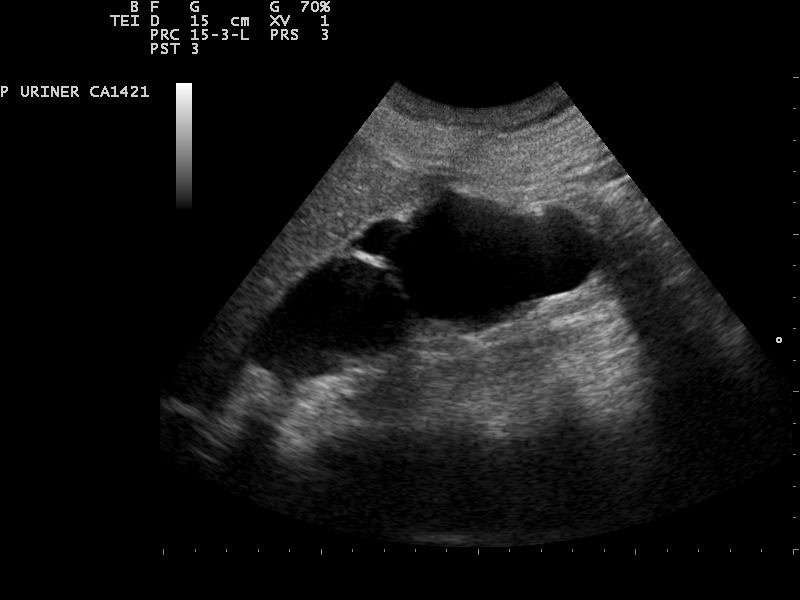

Sonografie der Harnblase

TippDie Sonografie der Harnblase gelingt am besten im gefüllten Zustand. Bei einem Füllungszustand unter 100 ml ist die Beurteilbarkeit eingeschränkt.

Durchführung

- Zur Untersuchung eignet sich - wie bei der Niere - ein konvexer Abdomenschallkopf

- Der/Die Patient:in liegt in Rückenlage

- Der konvexe Adomenschallkopf ist im mittleren Unterbauch anzusetzen

- Die Darstellung erfolgt zuerst im Querschnitt; anschließend im Längsschnitt, durch Rotation des Schallkopfs um 90°

- Bei Männern kann unterhalb der Harnblase die Prostata geschallt werden, bei Frauen Vagina

, Uterus und Rektum

Befundung

- Form: im Querschnitt annähernd rechteckig und dreieckig im Längsschnitt (abhängig vom Füllungszustand)

- Wanddicke: 3-5 mm bei gefüllter Harnblase

- Echogenität: echofrei

- Harnblasenvolumen: Männer max. 750 ml, Frauen max. 550 ml

- Berechnung in ml

- Länge und Tiefe im Längsschnitt und Breite im Querschnitt

- Formel: V(Harnblase) = Länge (cm) x Breite (cm) x Tiefe (cm) x 0,5

Exkurs: Restharnsonografie

- Dient der Feststellung einer Entleerungsstörung

- Untersuchungsbeginn: nach Entleerung der Blase

(nach Miktion) - Mittels Sonografie wird die verbliebene Harnmenge (Restharn) bestimmt

- Vermessung in cm von Querschnittslänge und -breite sowie Längsschnitthöhe

- Formel: V (Restharn) = Länge × Breite × Höhe × Korrekturfaktor (0,5 – 0,7)

- Restharnvolumen: <100ml

Pathologie

- Fehlbildungen, Festkörper (Konkremente), Blutkoagel, Raumforderungen (Harnblasentumor)

- Eine Verdickung der Blasenwand oder einer Restharnmenge von >100 ml können Zeichen einer Blasenentleerungsstörung sein